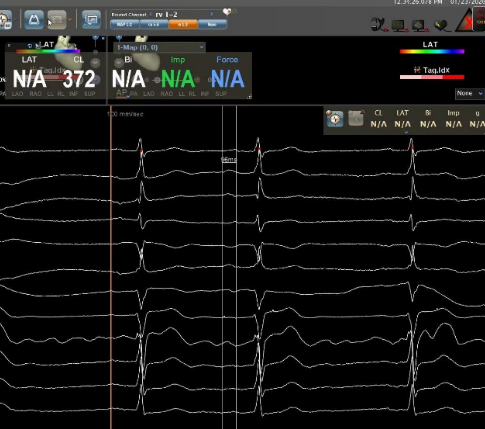

自身:P波宽度96ms,PR间期215ms

Bachmann束区域起搏:P波宽度75ms,PR间期185ms